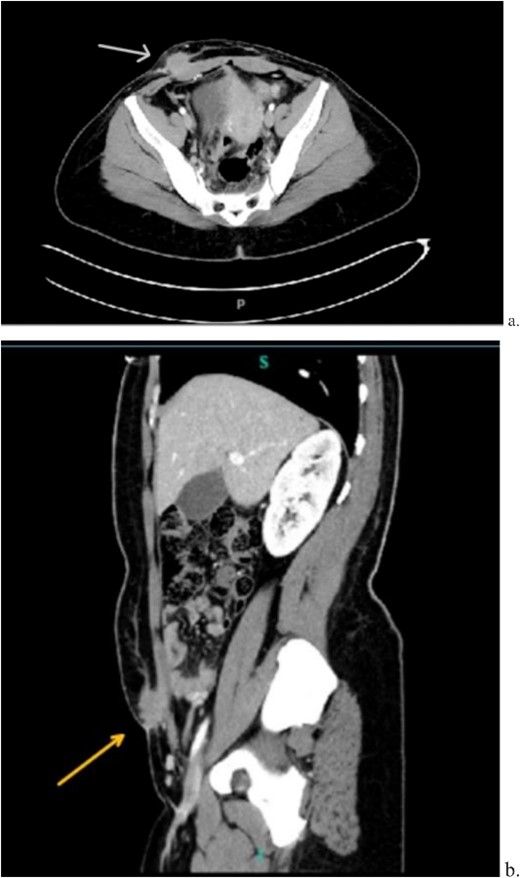

A 33-year-old female with past medical history of uterine fibroids and cervical insufficiency was initially seen with peri-incisional pain at the site of her Pfannenstiel scar since an emergency Cesarean section 16 months prior for eclampsia. She reported cyclical pain since that time, worse during menstruation and associated with swelling that resolved after menstruation. The discomfort and swelling persisted for 1 week after her last menstrual period, which prompted her to present for evaluation. On examination, a palpable, exquisitely tender mass was appreciated over the right side of her Pfannenstiel incision without evidence of discharge, erythema, or ulceration. Laboratory workup proved normal, and CT imaging revealed a soft tissue abscess-like collection anterior to the rectus abdominis muscle in the lower abdomen measuring 2.2 cm without intra-abdominal involvement (Fig. 9a and b). We deemed her a candidate for operative intervention given a high suspicion for endometrioma and her symptomatology.

Computed tomography axial (a) and sagittal (b) views of a 2.2 × 2.0 cm enhancing mass on the abdominal wall (arrows).